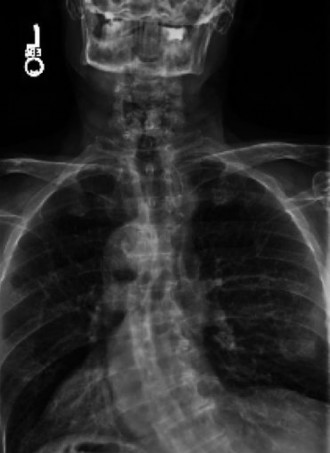

Expected surgical outcomes following revision surgery for recurrent disc herniation? CASE 3 A 27-year-old previously healthy woman is transferred directly to your trauma center with severe low back pain after jumping from an overpass in an apparent suicide attempt. The trauma team completes the primary survey, and the patient is hemodynamically stabilized with fluid resuscitation. On secondary survey she is found to have significant pain with examination/manipulation of her pelvis. Lower extremity examination demonstrates multiple superficial abrasions and grade 4/5 strength with great toe extension and ankle dorsiflexion on the left. Inspection of the perineum shows no blood at the urethral meatus or rectum; however, rectal tone and perianal sensation are decreased. The remainder of the examination is unremarkable. An anteroposterior view of the pelvis demonstrates unilateral superior and inferior rami fractures and a right L5 transverse process fracture.

The correct answer is (C). It is important to recognize that plain radiographs may only detect 30% of sacral injuries. This patient’s plain x-ray findings are highly suggestive of more substantial injuries than isolated rami fractures and transverse process fractures. In fact, the transverse process fracture should be assumed to have occurred by avulsion via the lumbosacral ligaments, which suggests large displacement of the hemipelvis. While plain radiographs may demonstrate sagittal displacement of sacral fractures, they are often of poor quality and do not enable

delineation of the entire fracture pattern. A pelvic computed tomography (CT) scan is indicated to better evaluate the bony injury as well as canal encroachment, particularly in the setting of a neurological deficit. An angiogram might be indicated if the patient was hemodynamically unstable and an intrapelvic bleed was suspected. CT scan images of the above patient are shown inFigures 1–8 and 1–9. Definitive management of this injury should be: 1. 3 months of bed rest followed by progressive mobilization

Figure 1–8 Mid-sagittal image of the pelvis.

Figure 1–9 Axial image of the pelvis.

The correct answer is (D). Critical steps in decision-making include determination of neurologic status, presence of associated pelvic ring injuries, and stability of the lumbopelvic junction. The neurologic examination demonstrates a deficit that is at least in part localized to the sacral nerve roots. In the presence of sacral canal compromise, decompression via laminectomy is indicated. The CT scan demonstrates a U-type injury with a high transverse sacral fracture and bilateral vertical extension through the sacral foramen. In the descriptive classification of sacral fractures in Denis zone 3, H-type and U-type sacral fractures represent spinopelvic dissociation and must be distinguished from fractures localized to the posterior pelvic ring, which are vertically unstable. The spinopelvic junction serves as a critical transitional zone as the axial load of the upper body is distributed from the upper sacrum to the ilium and finally the acetabulum. Surgery is indicated to prevent progressive deformity and chronic pain. Reconstruction should include stabilization from the lumbar spine to the pelvis using a pedicle screw/iliac screw construct. Nonoperative treatment with progressive mobilization is not appropriate for this type of fracture. Plating of the sacrum is not sufficient to restore stability of this injury; nor are sacroiliac screws.